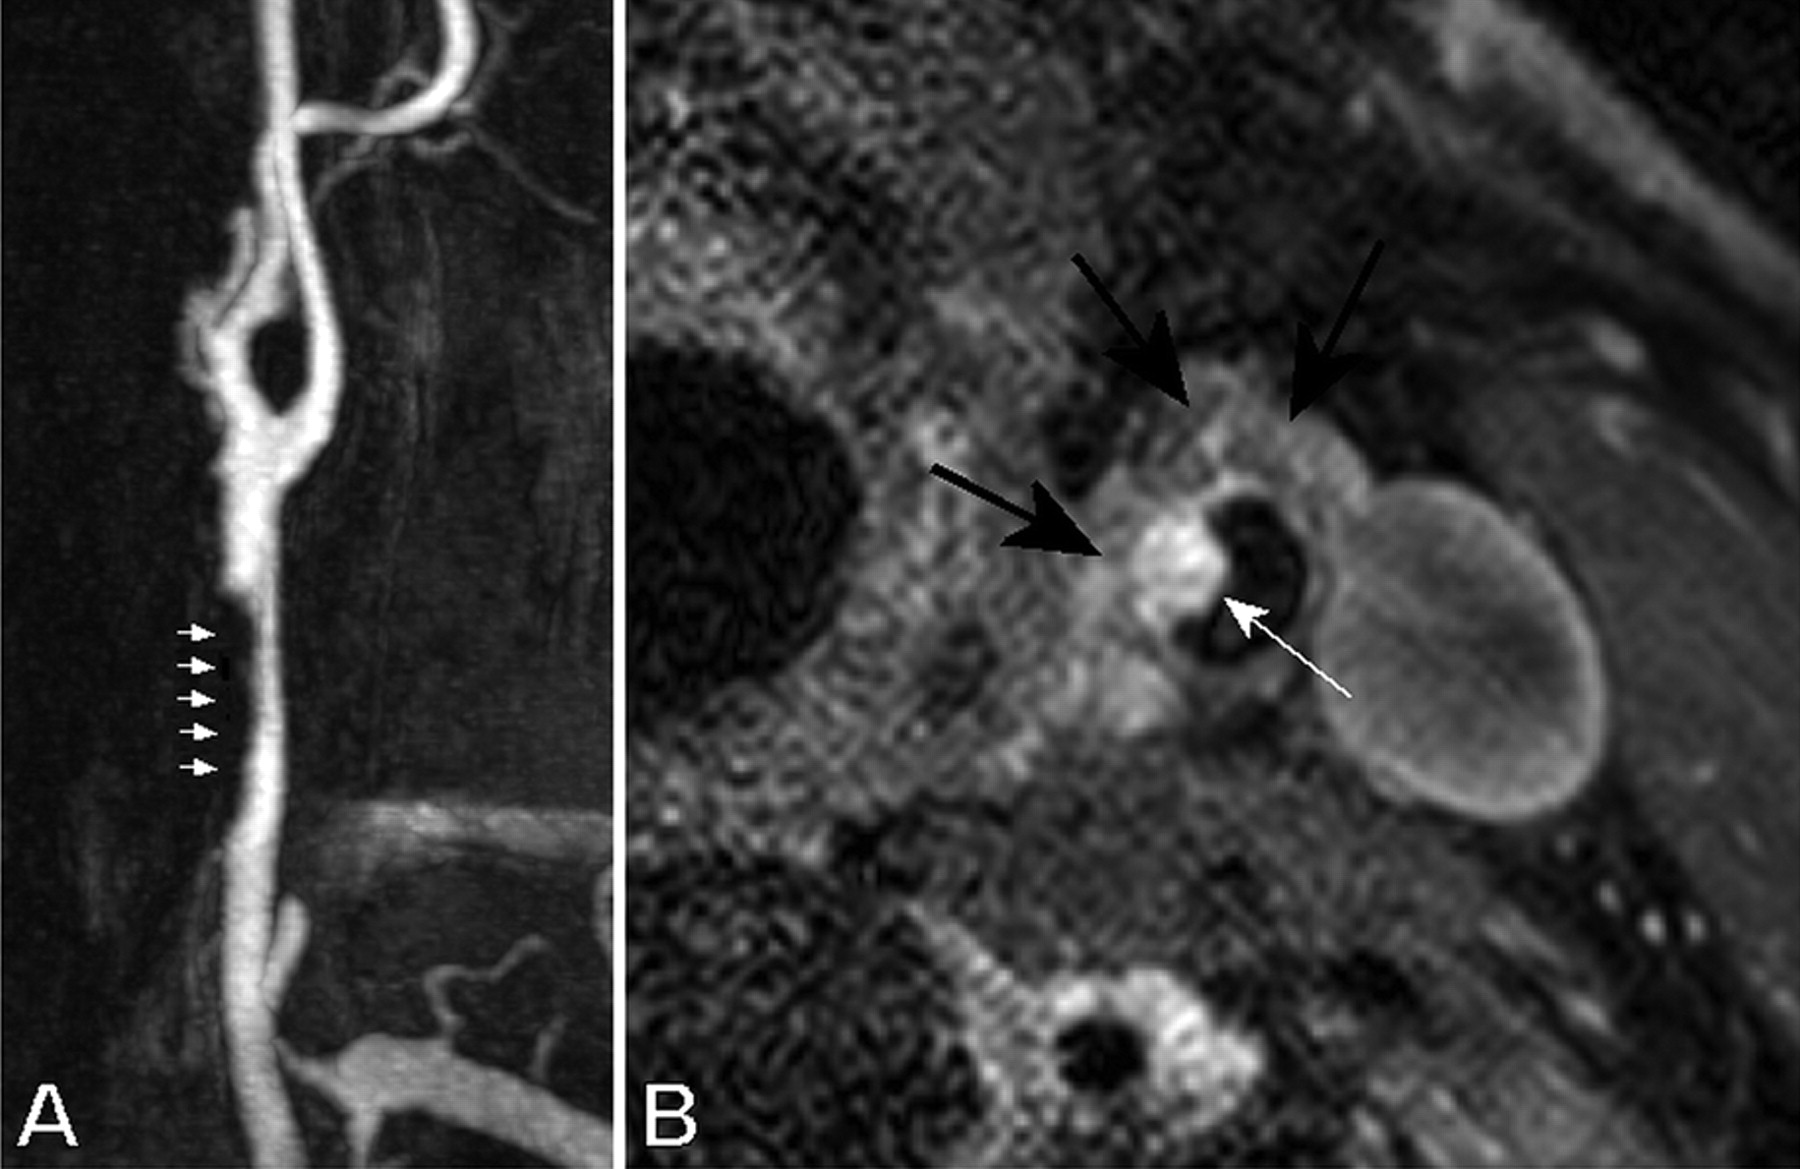

高分辨率核磁共振成像的孤立的颈总动脉管腔内的凝块

l . Boussel,p .杜克,n Nighoghossian